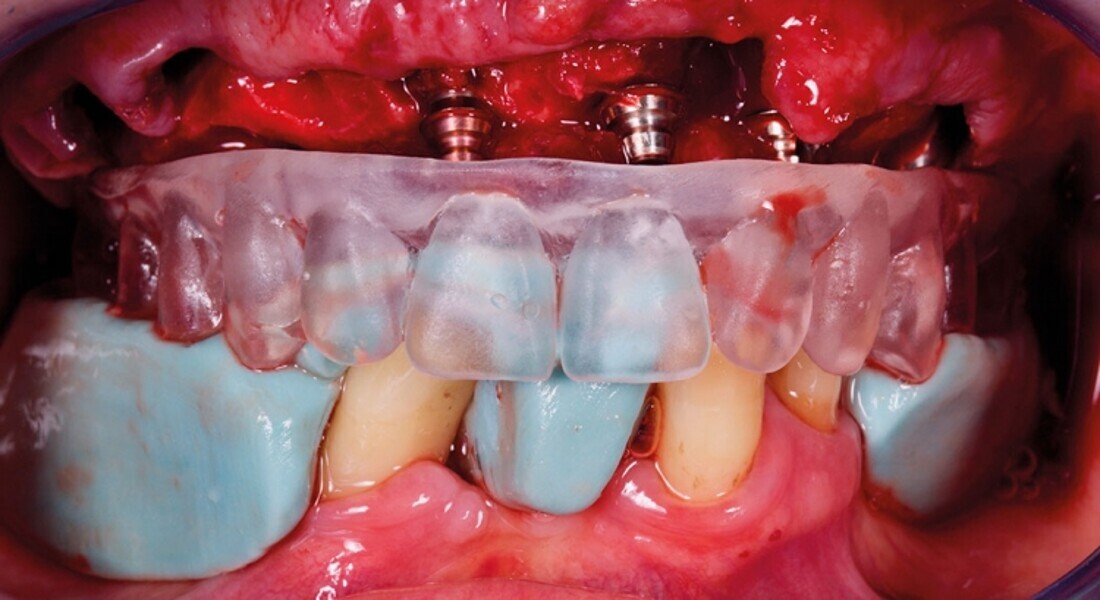

Protocollo SKY fast & fixed